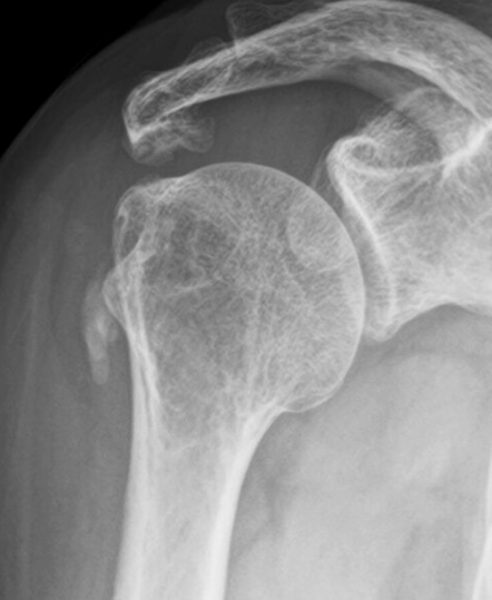

症例(60歳代女性)

2日前から右肩が急に痛み出し、夜も眠れない状態で来院。

レントゲンで石灰を確認し、エコーガイド下で吸引とステロイド注射を実施。直後から痛みは消失。

10日後、石灰は消失しました。

初診時のレントゲン:石灰が確認できます

10日後に石灰は完全に消失しています